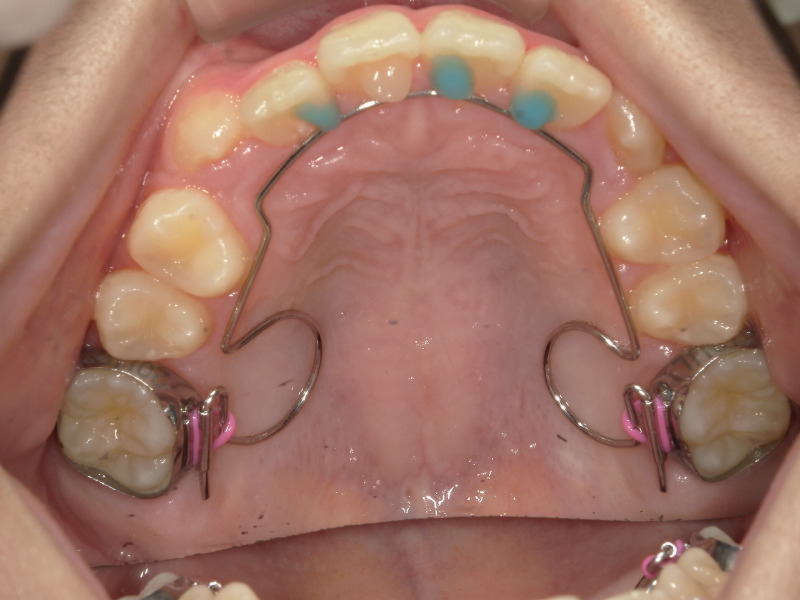

装置の併用

bwsセット

8歳のスタートということもあり、時間にはまだ猶予がありますが上顎の成長のピークは終わりに近いです。

3番目の歯が生えてきた頃の顎の状態などを確認して併用する装置を入れることになりました。